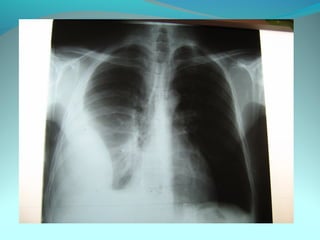

Opacité dense et homogene occupant les 2/3 sup du poumon droit a

limite super extr se confond avec le mediastin et la limite infer

convexe vers le bas

Cette opacité est le siege d une clarté séparée d’elle par un niveau

horizontal

DIAGNOSTIC:

Pneumonie excavée droite

Cancer bronchique excavé